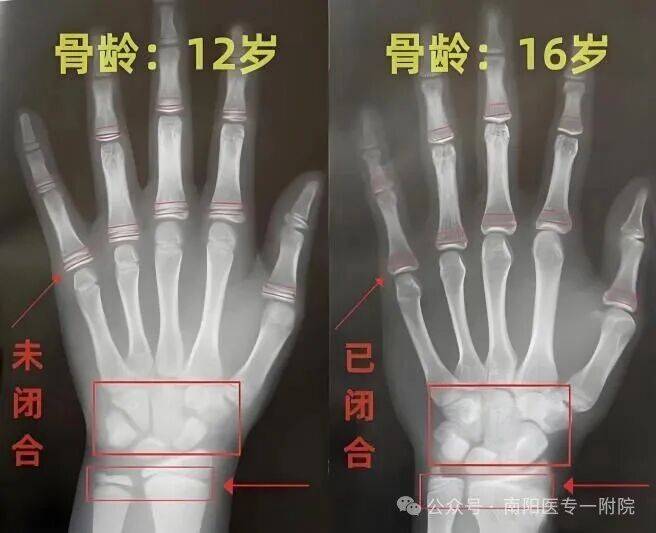

人的生长发育可用两个“年龄”来表示,即生活年龄(日历年龄) 和生物年龄(骨龄)。骨龄是骨骼年龄的简称,一般情况下与生活年龄相差在1年以内。但在疾病的影响下,骨龄可能严重落后或提前。骨龄能够较为准确地反映人体的生长发育情况和身高增长空间,当生长板(骨骺线)完全闭合时,身高也就失去了线性增长的机会。因此,测骨龄是临床诊疗矮小症必须做的检查项目之一。